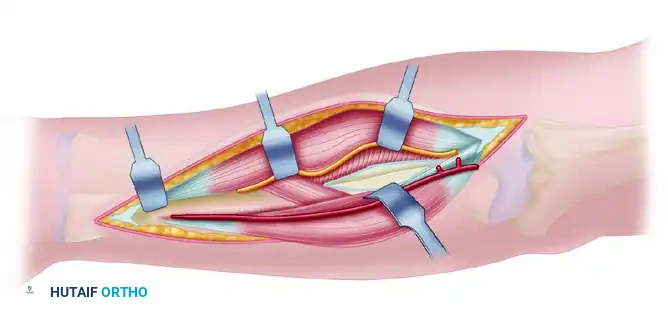

To minimize the risk of radioulnar synostosis, the radius and ulna must be approached through separate incisions. The choice of approach depends on the level of the fracture.

The Volar Henry Approach to the Radius

For the vast majority of fractures involving the middle and distal thirds of the radial shaft, the volar Henry approach is preferred. It utilizes the internervous plane between the flexor carpi radialis (FCR, innervated by the median nerve) and the brachioradialis (BR, innervated by the radial nerve).

Superficial dissection involves incising the deep fascia in line with the skin incision. The radial artery must be identified and protected, usually retracting it medially with the FCR.

In the proximal extent of the wound, the radial recurrent artery and its venae comitantes must be ligated and divided to allow lateral retraction of the brachioradialis and the superficial branch of the radial nerve.

Deep dissection requires the elevation of the supinator muscle. To protect the posterior interosseous nerve (PIN) within the supinator, the muscle must be detached from its ulnar and volar insertions and reflected laterally.

1. Exposure and Debridement

Following the chosen surgical approaches, expose the fracture sites. It is imperative to preserve the periosteum along the proximal and distal segments to maintain the osteogenic potential of the bone. Do not strip the periosteum beyond what is absolutely necessary for plate application. Débride the fracture edges, meticulously removing interposed hematoma, muscle, and devitalized debris to allow for intimate cortical contact.